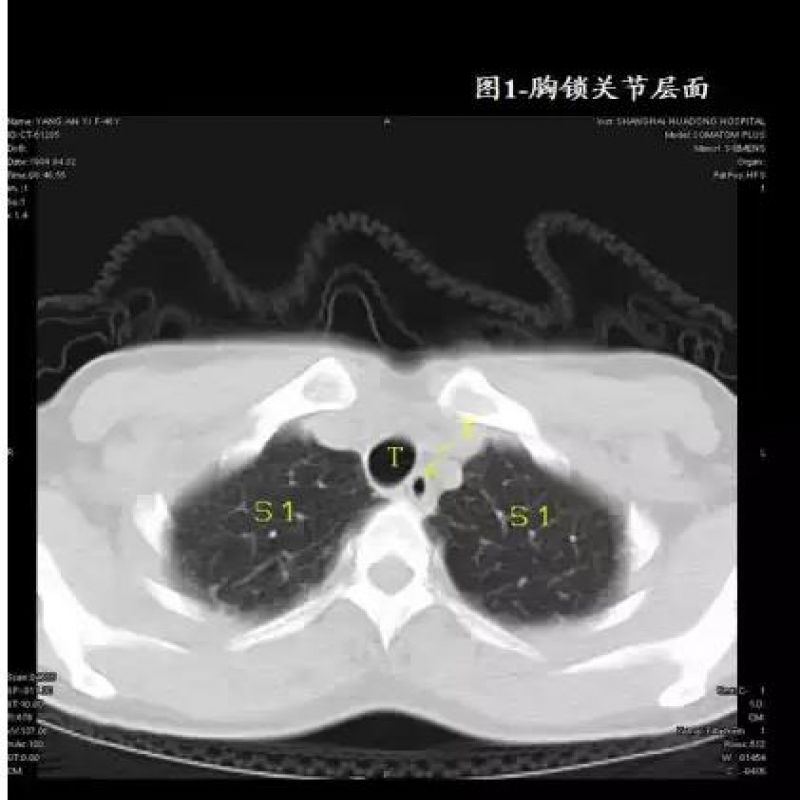

还在为胸部 CT 解剖 “一头雾水”?麻醉同行必备影像速查手册!